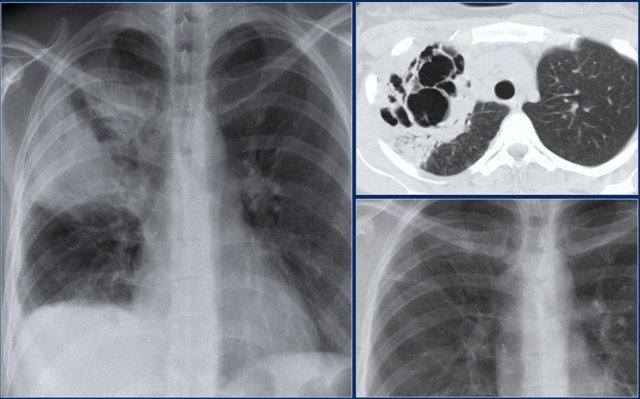

Trong trường hợp này, có một số cấu trúc dạng khối ở phổi phải.

CT đã chứng minh giãn phế quản kèm tắc nghẽn do nhầy.

Một biểu hiện phổ biến hơn của tắc nghẽn do nhầy được thấy ở đây.

Đây là hình ảnh điển hình ‘ngón tay trong găng tay’ của tắc nghẽn do nhầy.

Chất nhầy trong các phế quản giãn trông giống như các ngón tay trong một chiếc găng tay.